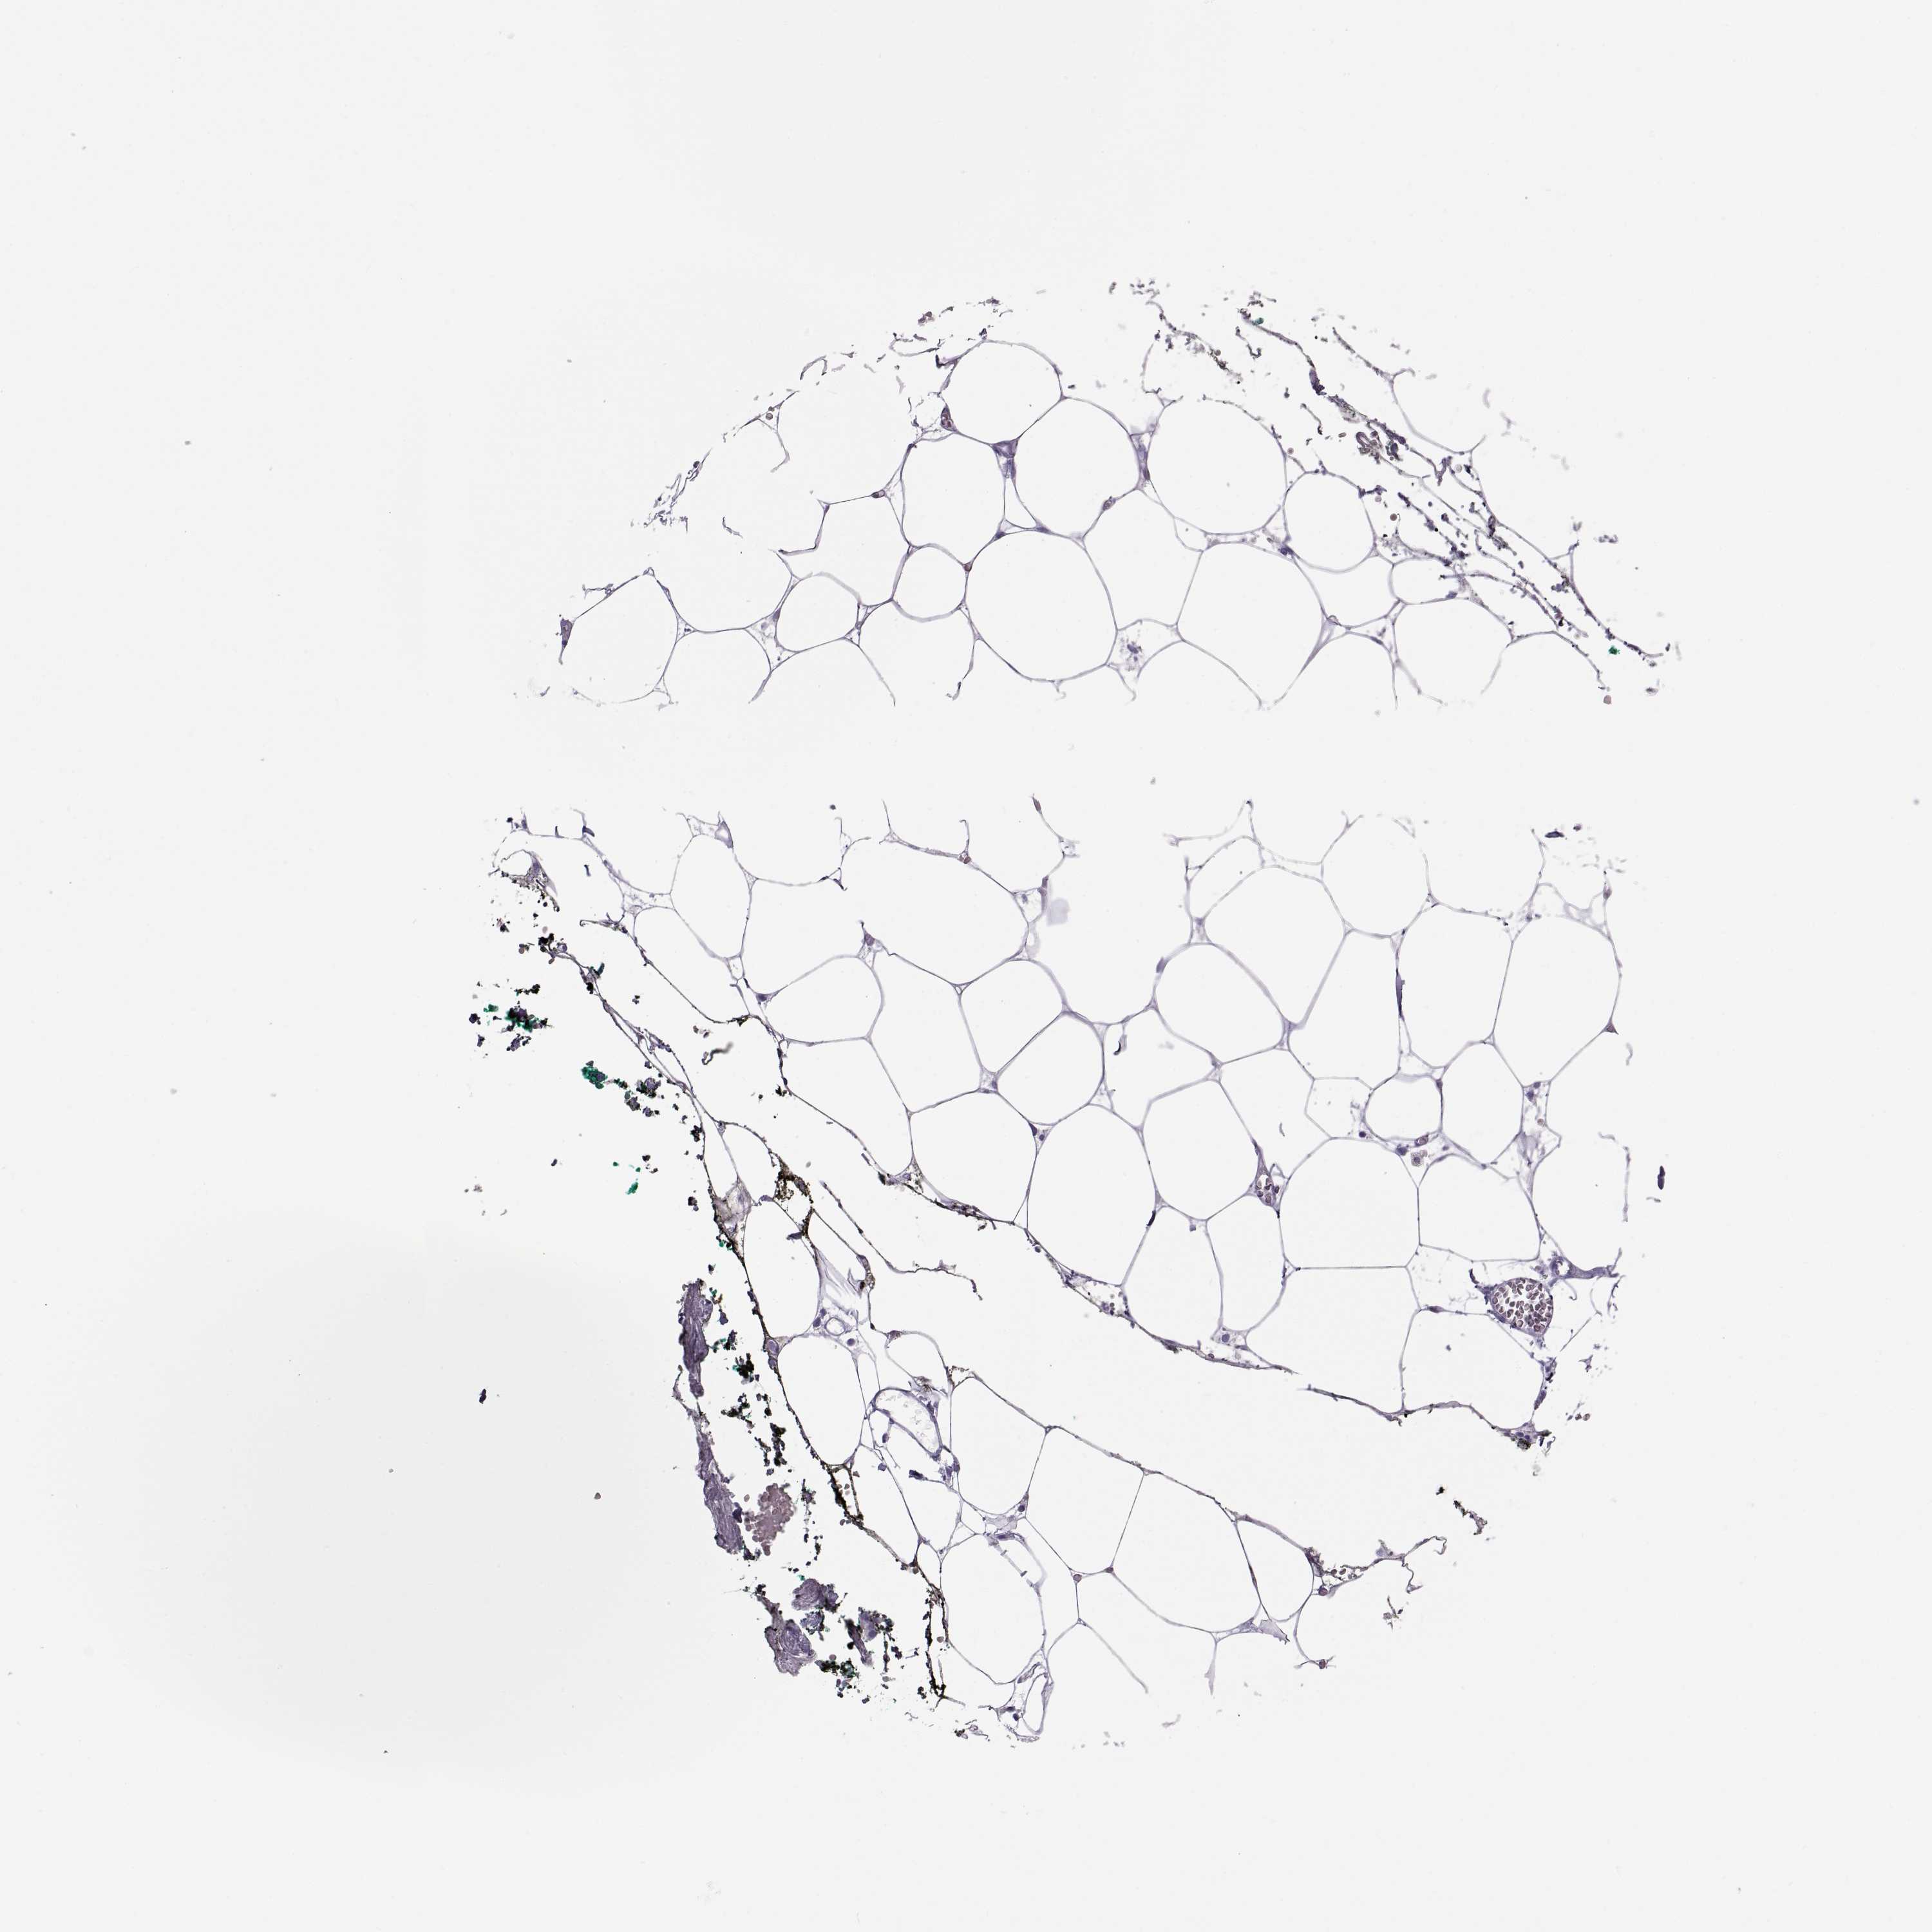

ADIPOSE TISSUE - Antibody stainingi

Antibody staining in the annotated cell types in the current human tissue is reported as not detected, low, medium, or high, based on conventional immunohistochemistry profiling in selected tissues. This score is based on the combination of the staining intensity and fraction of stained cells.

Each image is clickable and will lead to virtual microscopy that enables deeper exploration of all samples and also displays staining intensity scores, fraction scores and subcellular localization as well as patient and tissue information for each sample.

Antibody HPA042476Antibody HPA064892

Adipocytes Not detectedNot detected